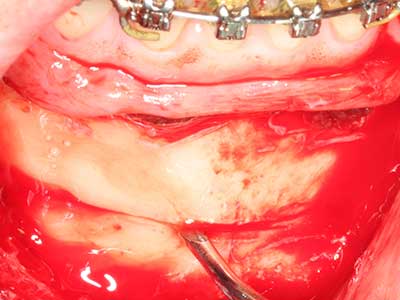

Abb. 21: Ausgedehnter OK-Frontzahndefekt mit Indikation zur Distraktionsosteogenese bei vernarbtem Weichgewebe nach Vor-Operation.

Abb. 22: Das mobile Segment kann präzise mit der dünnen Osteotomiesäge (W&H Piezomed) separiert werden.